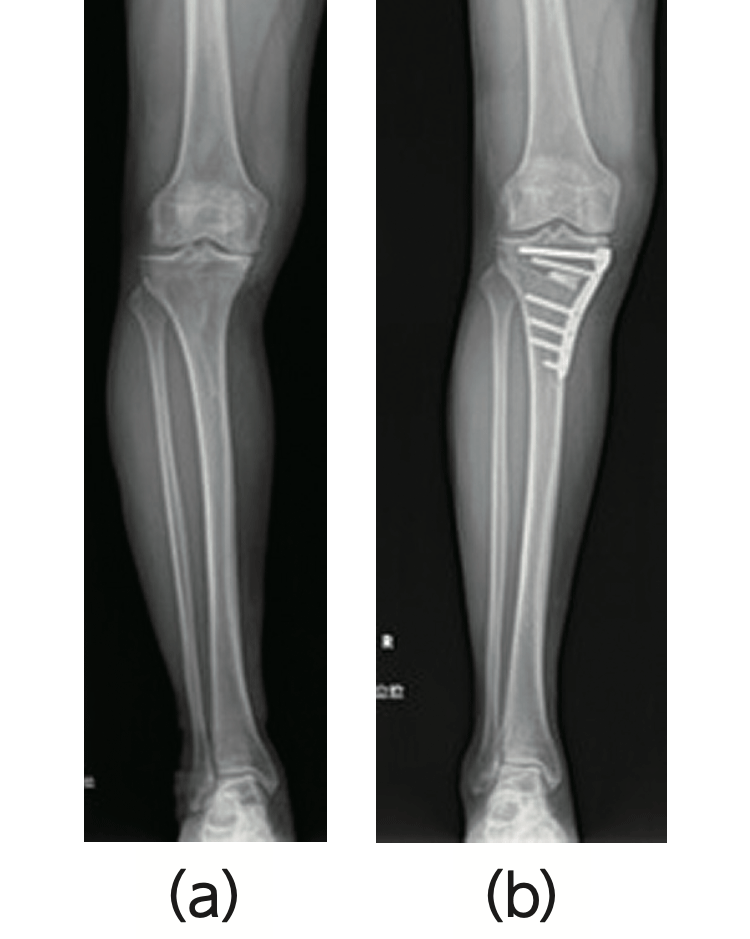

- ・膝周囲骨切り術(図1)

- 変形が膝関節内の内側または外側の一方に限られ、O脚やX脚変形を生じた、活動性の高い比較的若年者に行います。

内側型の変形性膝関節症によるO脚変形(a) を、外科的に骨切りし、ややX脚に矯正します(b)